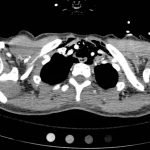

Anteroposterior (AP) chest X-ray showed subcutaneous emphysema of the neck, surrounding the trachea (red arrows), right side greater than left, and a streak of gas adjacent to the aortic arch (white arrow). Computed tomography angiogram (CTA) of the neck showed air outside of the trachea, positive for pneumomediastinum (blue arrows).